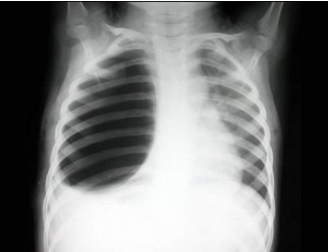

患者,男,3岁,突发左侧胸痛伴呼吸困难3小时入院,如图所示,最可能的诊断为()

A.左侧肺气肿

B.左侧气胸

C.左肺门淋巴结结核

D.右肺小叶性肺炎

E.以上都不正确